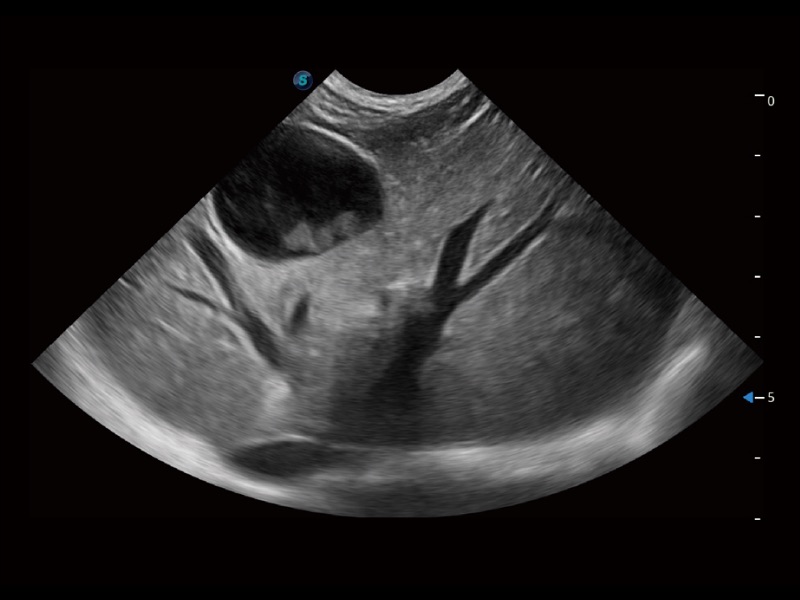

通过创新的 Matrix E自适应滤波器和超长时间域算法,极大提升超低速微细血流的检出能力,同时更精准地滤除软组织和噪声信号,为兽用医生提供以往无法通过常规血流获得的疾病诊断信息。